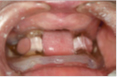

| Management of Obstructive Sleep Apnea in an Edentulous Lower Jaw Patient with a Mandibular Advancement Device [20] | 1. Aumenta la dimensión anteroposterior de la orofarínge 2. Fácil fabricación 3. Económico 4. Confortable | 1. Requiere preferiblemente de algunos dientes para mayor retención 2. Monobloque 3. Limita movimientos de lateralidad | 1. Protruir la mandíbula 2. Aumentar la dimensión vertical | ![]() |

Nayar y Knox [17], en el 2005, propusieron un aparato para el tratamiento de la AOS en edéntulos totales, donde el diseño incluyó una férula convencional maxilar realizada al vacío y una férula de avance mandibular, ambas soportadas por el tejido blando del paciente y unidas entre sí por acrílico autopolimerizable. La principal limitante de este dispositivo es que se dependía de la expansión de los flancos linguales que presentaba el paciente para lograr una retención adecuada.